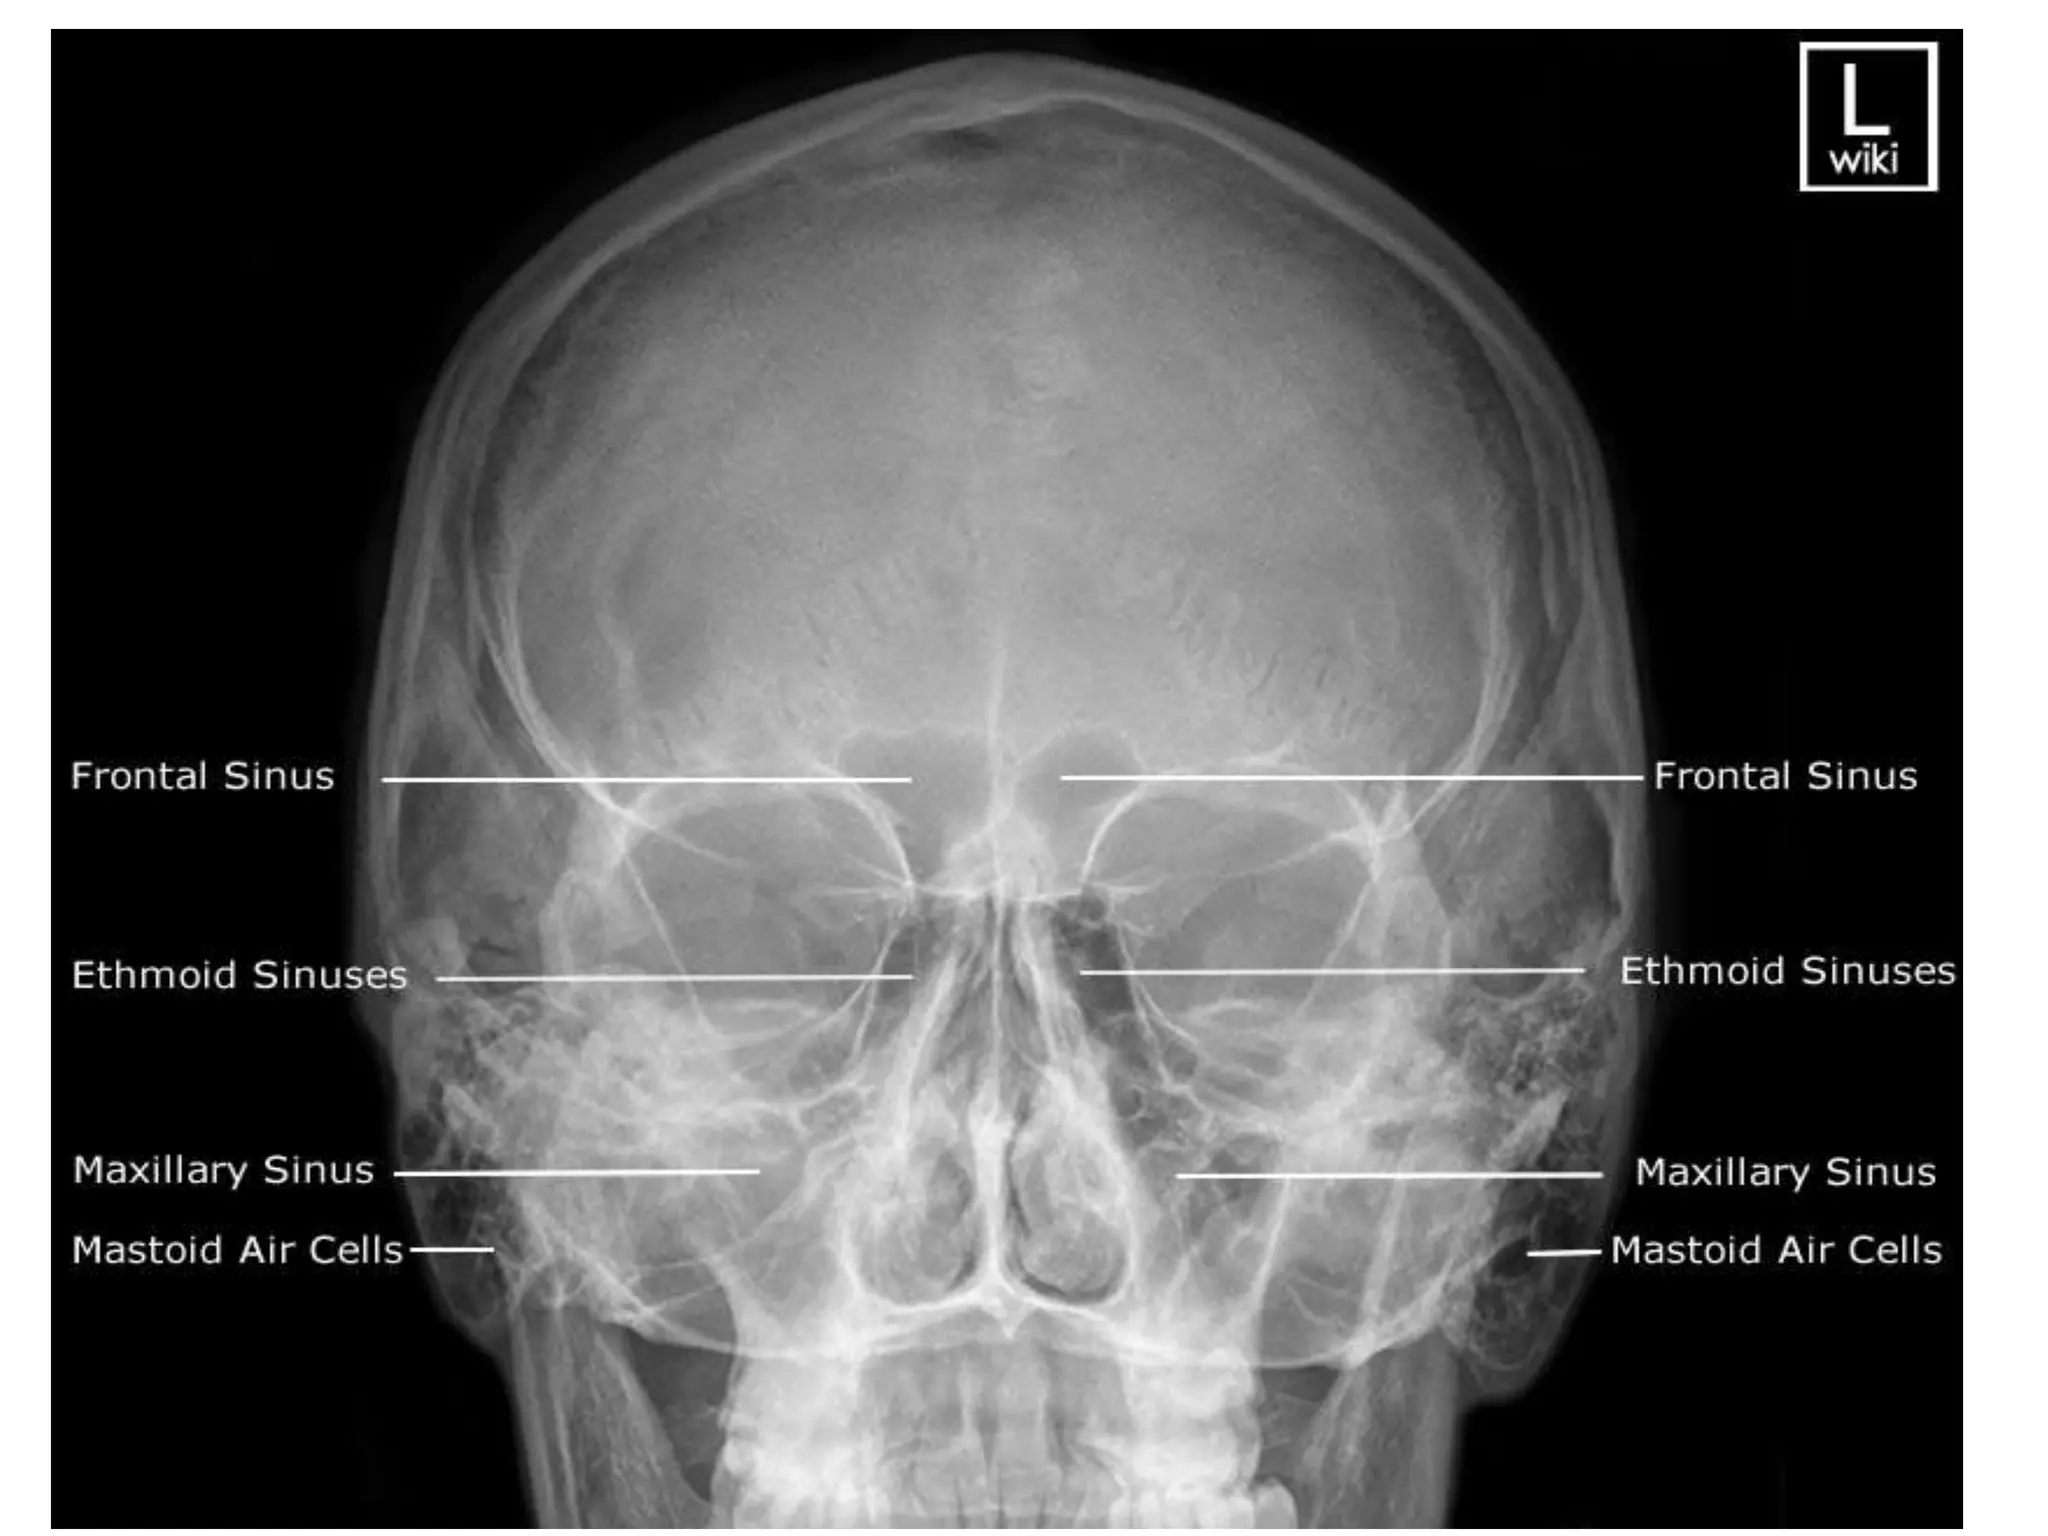

 X ray – Water’s view & caldwell view.

 CT – gold standard. Coronal & axial sections.